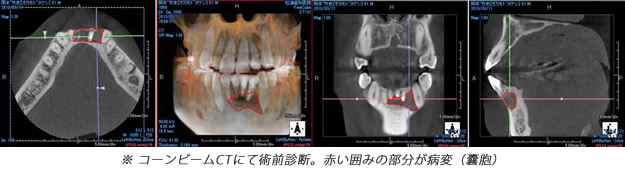

歯内療法か?外科的療法か?病理組織的には病変に上皮があれば歯根嚢胞(外科的療法必要)、上皮がなく繊維と血管だけの場合は歯根肉芽腫(歯内療法で治癒可能)と呼ばれますが、実際の所レントゲン(CTを含む)で判断するのは困難です。臨床の現場ではまず歯内療法のみを選択しますが、治癒しない場合は外科的療法(嚢胞摘出&歯根端切除術)に移行するといった流れになることが多いです。 |